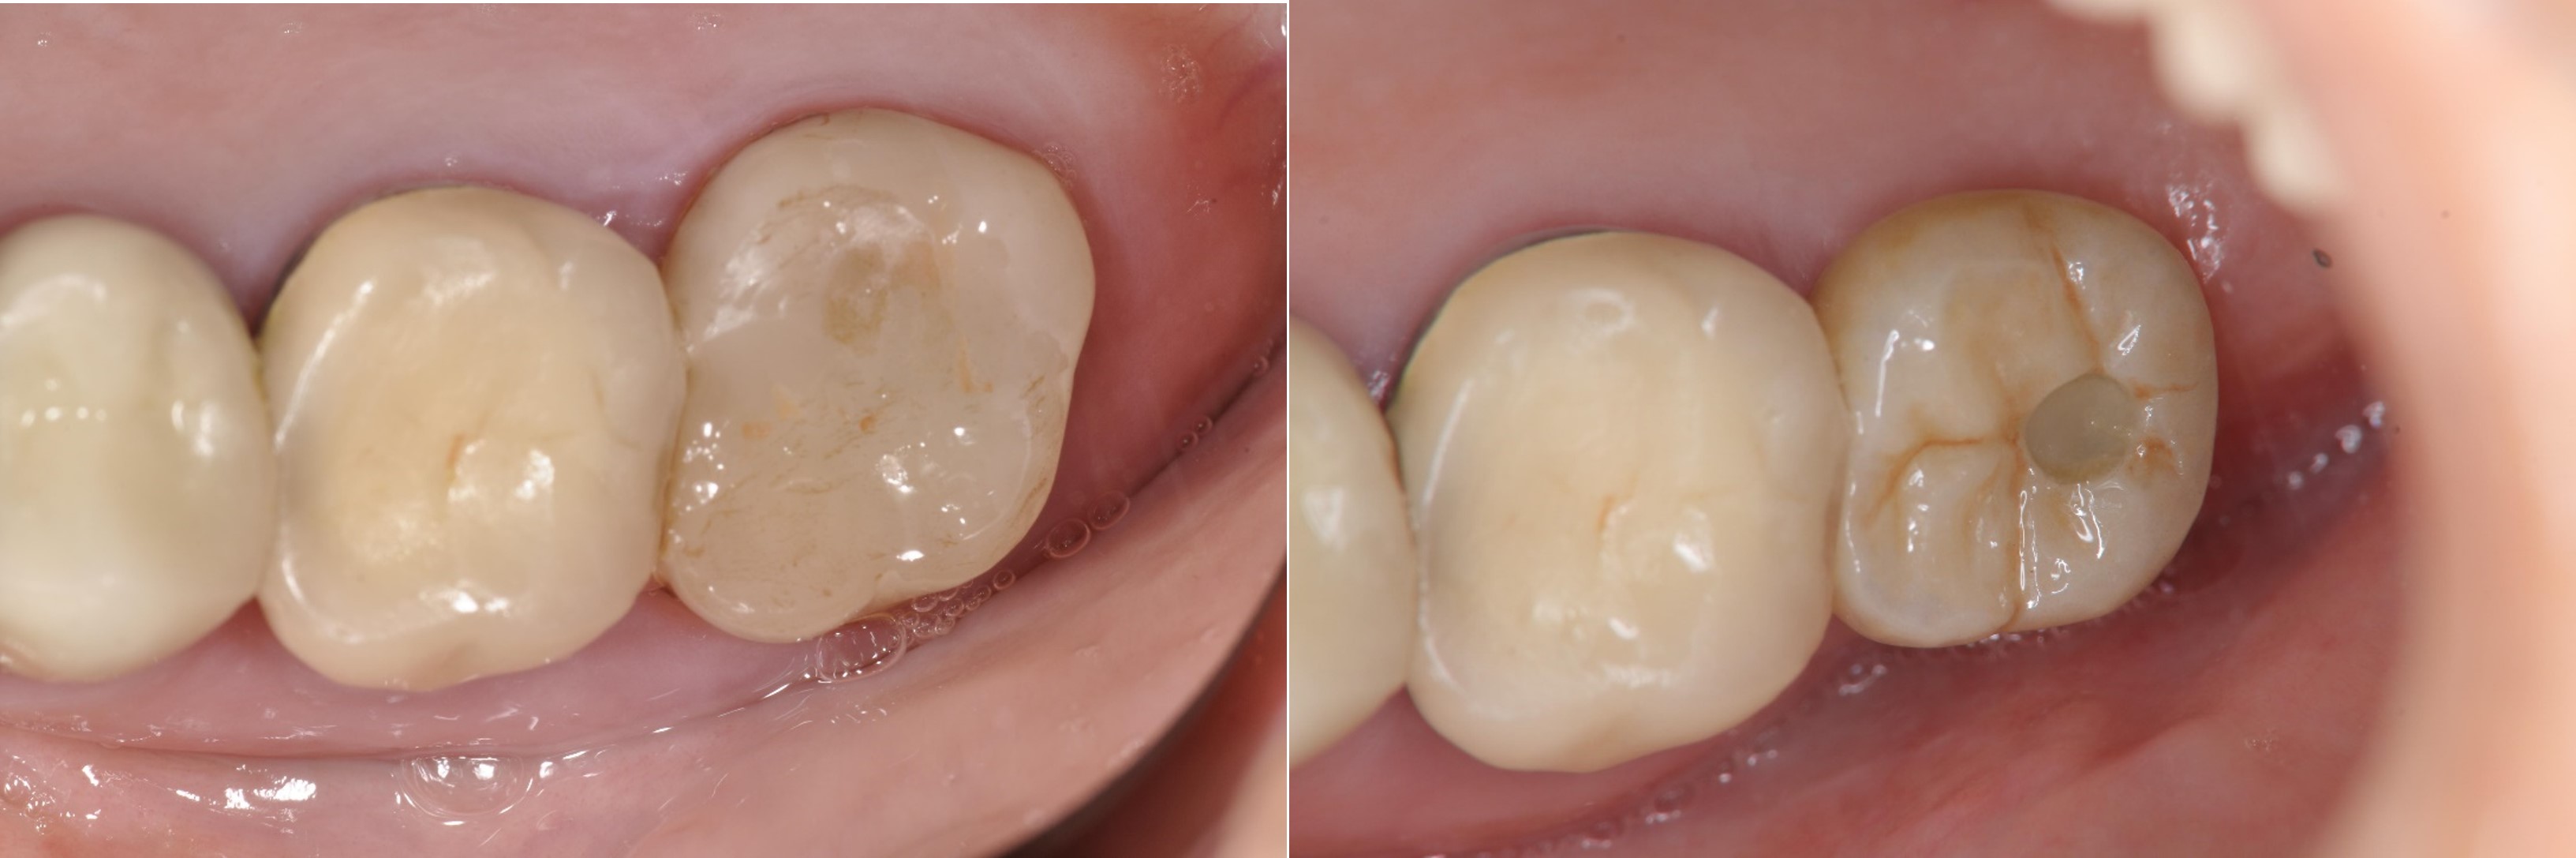

術前、術後比較

治療後,咬合牙周適應良好

治療後,密合度良好